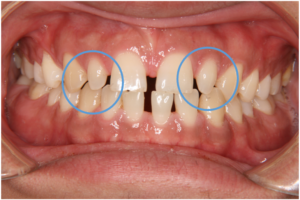

歯が重なって生えている部分や歯が外側に倒れている部分には元々歯を支える十分な骨(歯槽骨)がありません。そのため、歯並びの改善により移動してきた歯の周りに歯茎や骨が新たに理想的な状態で再生する可能性は低く、どうしてもBTが形成されやすくなります(図8)。この傾向は歯の移動量が多いと増強され、さらに上記のような様々な原因が重なることで、よりBTがより発生しやすくなります。

下顎前歯部の叢生

↓↓↓

わずかなブラックトライアングル

図8 デコボコのある部分の治療前後の変化(元々骨のないところに並んでいた歯が整列ししているため、歯茎や骨は完全には再生できていない)